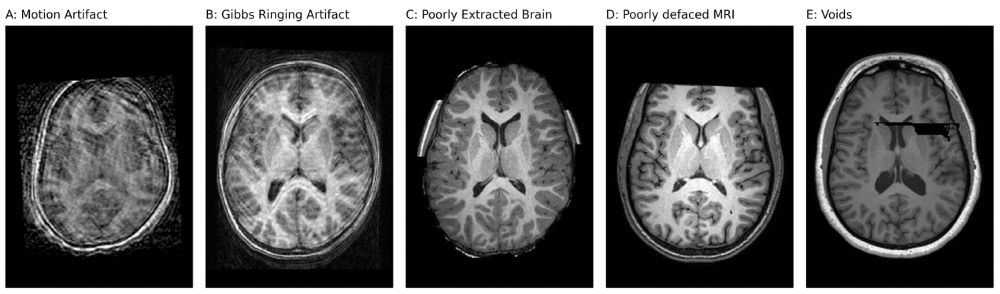

New paper in Imaging Neuroscience by Muhammad Nabi Yasinzai, Remika Mito, and Mangor Pedersen:

BrainScape: An open-source framework for integrating and preprocessing anatomical MRI datasets